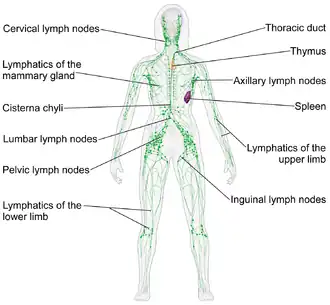

Immune system

The immune system consists of the white blood cells, the thymus, lymph nodes and lymph channels, which are also part of the lymphatic system. The immune system provides a mechanism for the body to distinguish its own cells and tissues from outside cells and substances and to neutralize or destroy the latter by using specialized proteins such as antibodies, cytokines, and toll-like receptors, among many others.[31]

Lymphatic system

The lymphatic system extracts, transports and metabolizes lymph, the fluid found in between cells. The lymphatic system is similar to the circulatory system in terms of both its structure and its most basic function, to carry a body fluid.[34]